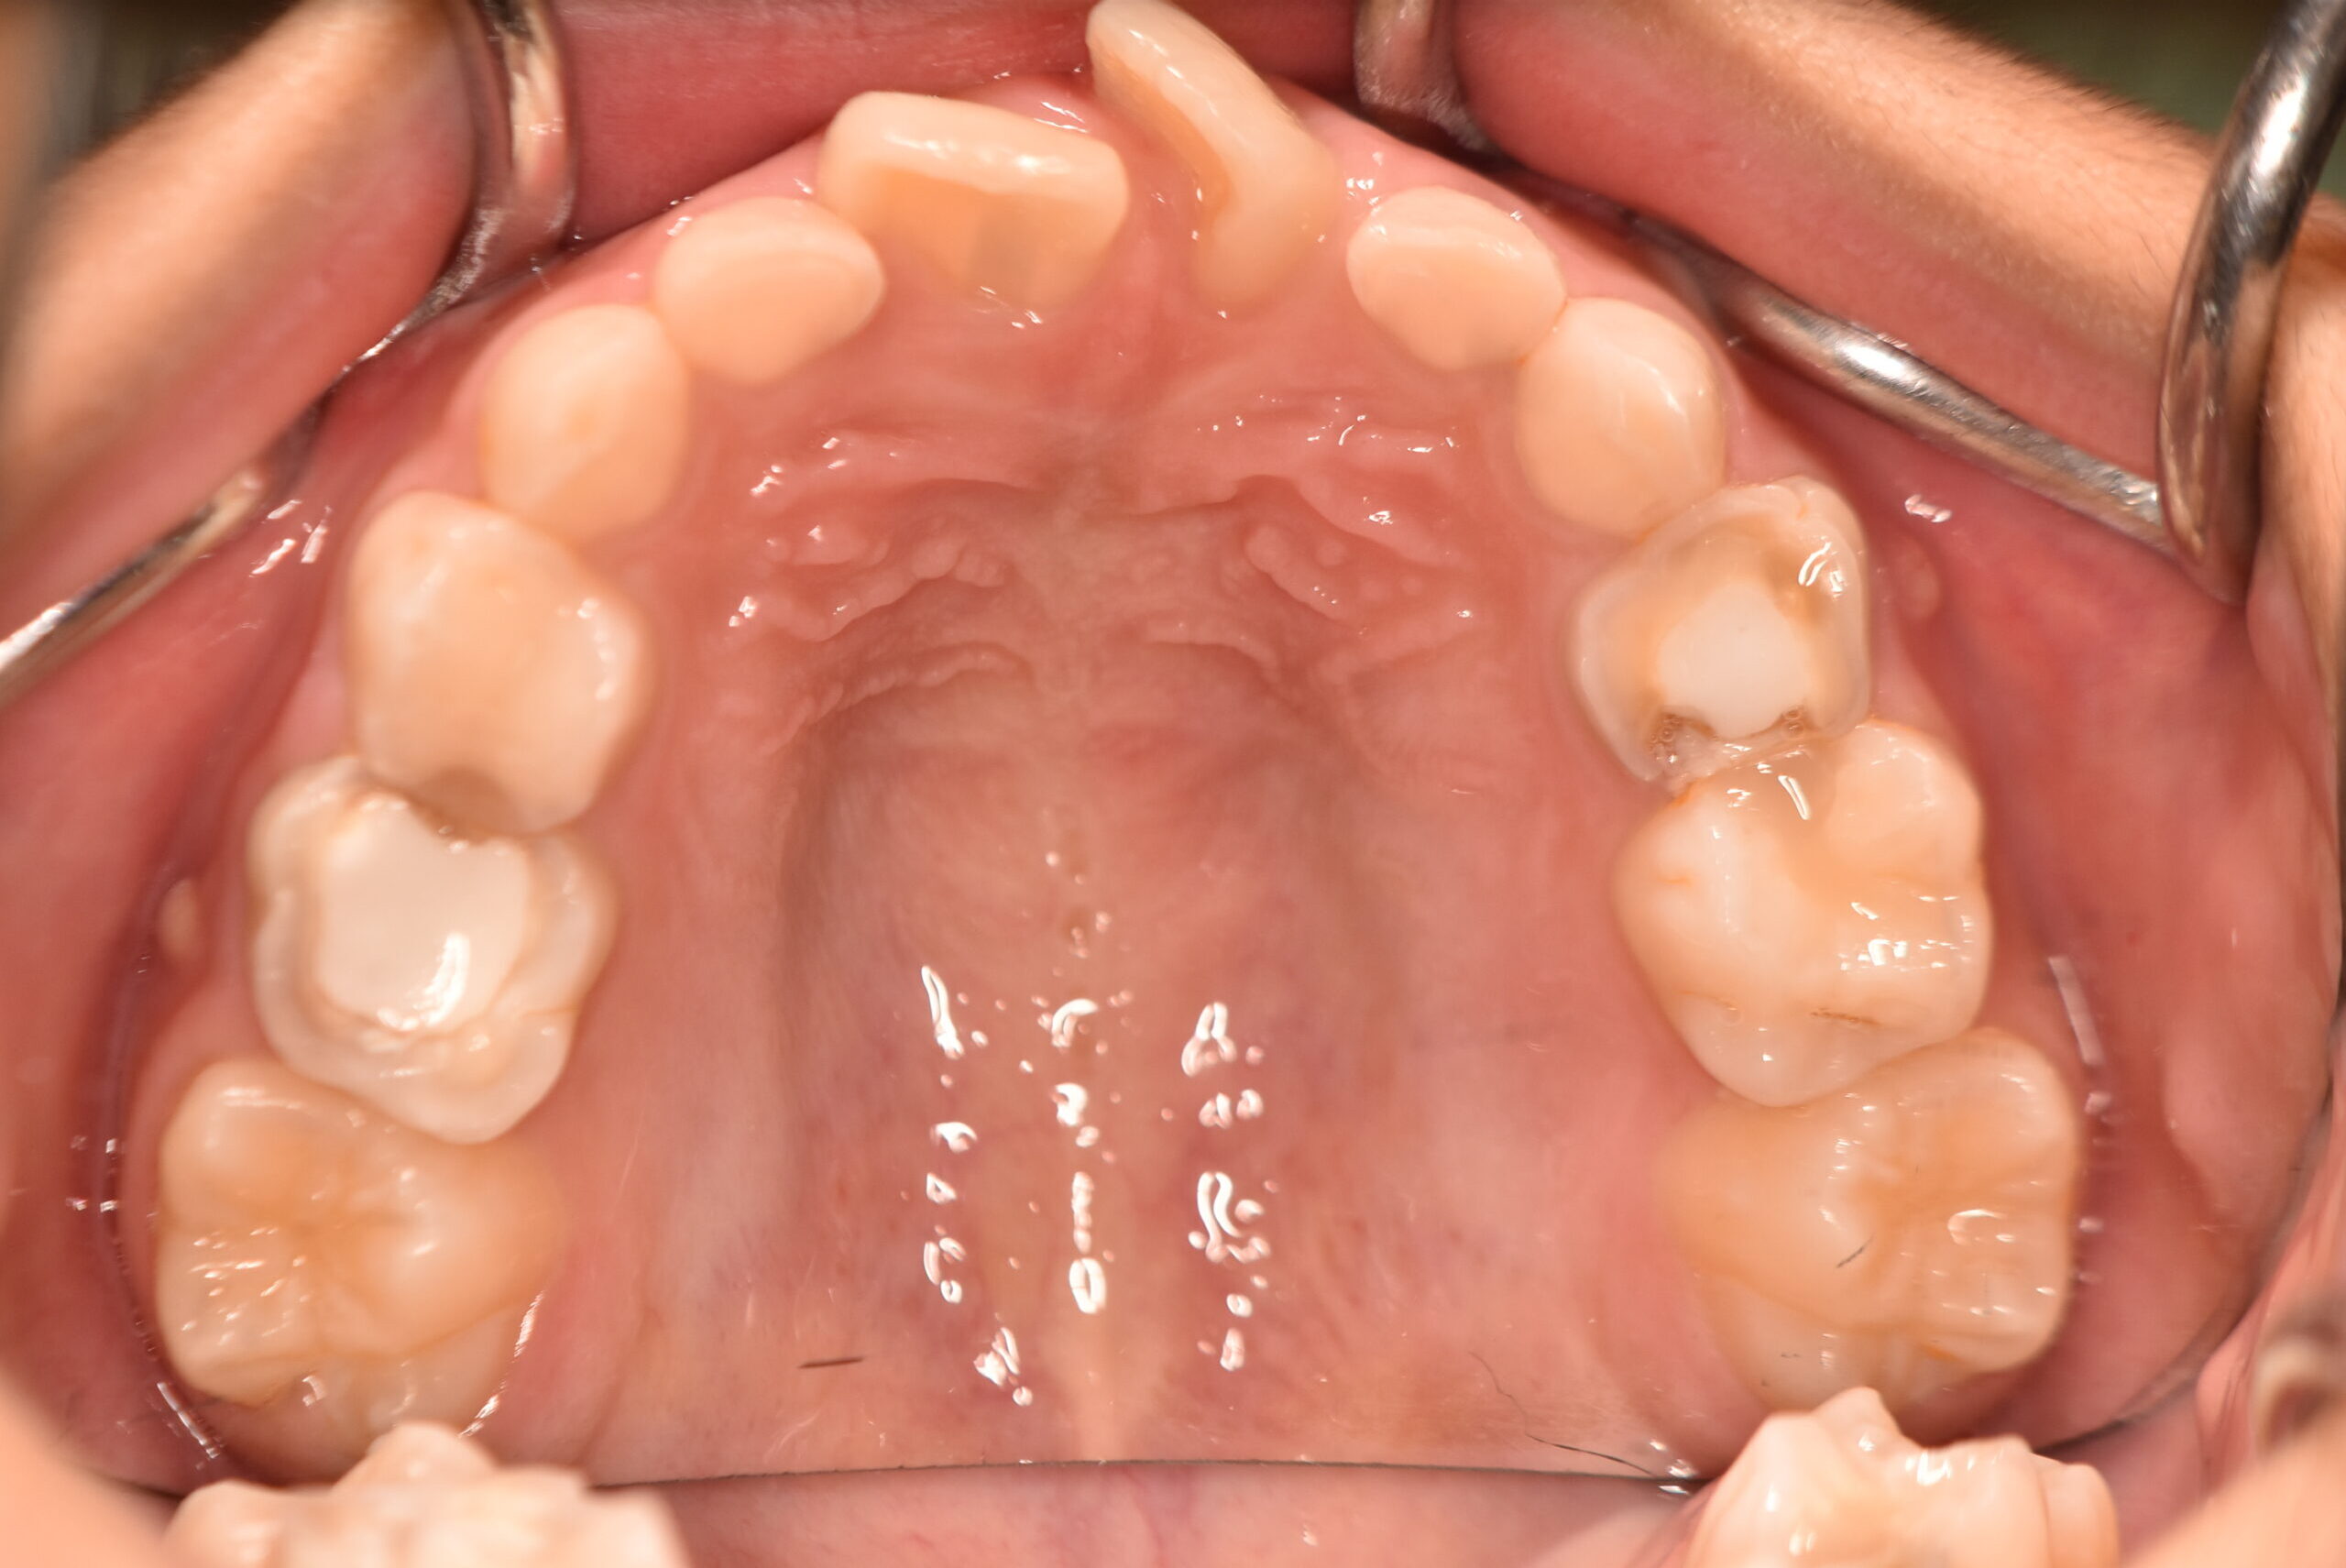

| 治療内容の詳細 | 初診時9歳3ヶ月の男児で、前歯が磨きにくく虫歯になりやすいことを気にされ来院されました。 検査の結果、前歯部叢生を伴うアングルⅠ級不正咬合と診断しました。 治療としてはマウスピース矯正(インビザラインファースト)で配列を行い、上下顎の側方拡大により永久歯の萌出スペースを確保しました。 治療期間は、1年6ヶ月でした。 今後、永久歯(側方歯)の生え変わりまで経過観察を行います。 |